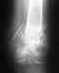

Здравствуйте! Меня интересует, можно ли в вашем УНИИТО сделать диагностику заболеваний стопы, суставов ног? Как долго это делается? Можно ли записаться на прием ? У меня артрозо-артрит голеностопных суставов, гоноартроз коленных суставов, артроз правого тазобедренного.3 месяца назад был перелом наружной лодыжки, подвывих стопы кнаружи,разрыв дистального межберцевого синдесмоза. В данное время перелом сросся нормально, но имеет место быть посттравматический остеопороз, периостит плюсневой кости. Нужна грамотная консультация.